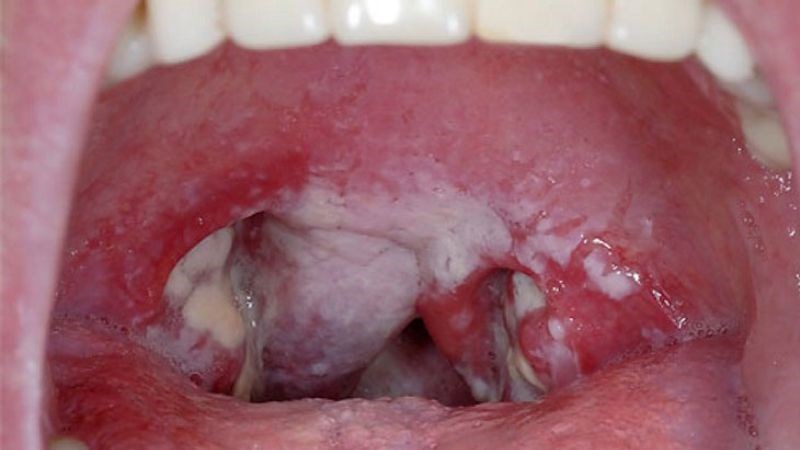

- Xuất hiện màng dày màu xám xung quanh các niêm mạc hầu, họng và amidan, rất khó để loại bỏ.

Bạch hầu sẽ tiết ra độc tố gây ra những màng dày bao quanh niêm mạc hầu, họng và rất khó để loại bỏ. Chính những màng dày này ngăn cản sự lưu thông không khí gây cản trở đường thở.

Bác sĩ tiến hành đánh giá các triệu chứng mà người bệnh gặp phải bao gồm đau họng, sốt, mệt mỏi. Ngoài ra, bệnh nhân sẽ được soi hầu họng để quan sát phần giả mạc đặc trưng của bệnh.

- Xuất hiện giả mạc màu xám khó bóc.